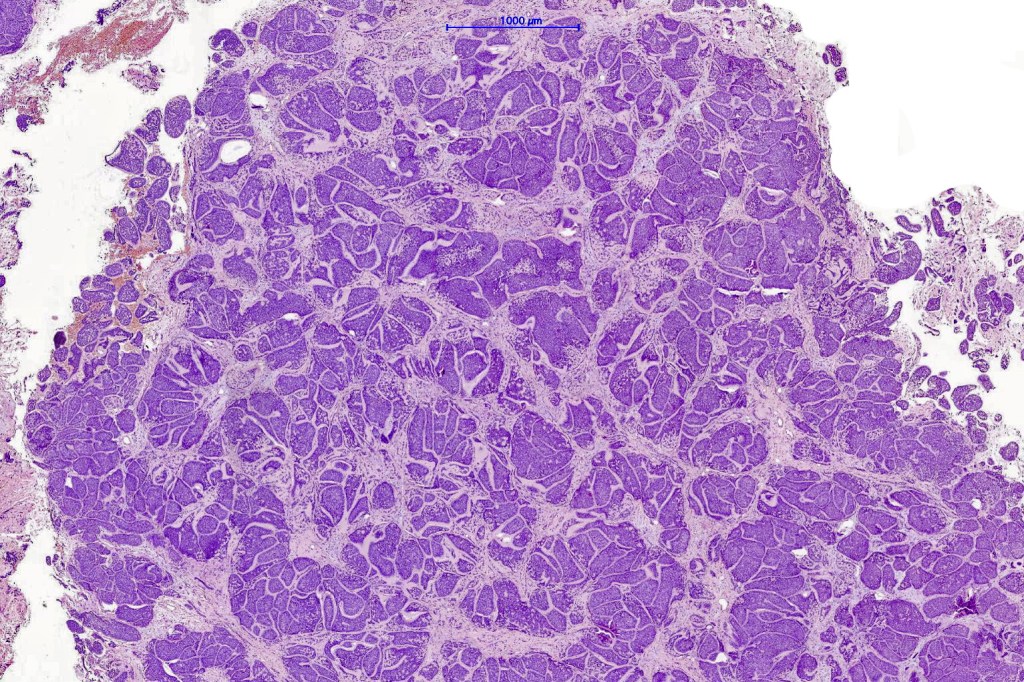

Histological features

•Dermal based

•Jigsaw/mosaic pattern arrangement of variably sized lobules of tumor cells with surrounding think, eosinophilic hyaline basement membrane

•Intralobular hyaline basement membrane material droplets

•Outer layer of intensely basophilic small cells surrounding larger central cells with pale staining or eosinophilic cytoplasm & vesicular nuclei

•Ductal differentiation